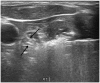

Radiofrequency ablation (RFA) is a well-known, effective, and safe method for treating benign thyroid nodules and recurrent thyroid cancers. Thyroid-dedicated devices and basic techniques for thyroid RFA were introduced by the Korean Society of Thyroid Radiology (KSThR) in 2012. Thyroid RFA has now been adopted worldwide, with subsequent advances in devices and techniques. To optimize the treatment efficacy and patient safety, understanding the basic and advanced RFA techniques and selecting the optimal treatment strategy are critical. The goal of this review is to therefore provide updates and analysis of current devices and advanced techniques for RFA treatment of benign thyroid nodules and recurrent thyroid cancers.